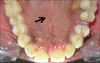

Turner's syndrome is a disorder in females characterized by the absence of all or part of a normal second sex chromosome. It is typically characterized by the combination of physical features and cytogenetics in females. Physical features include short stature, primary amenorrhea, hypogonadism, low hair line at the back of the neck, and digital anomalies. Most affected patients have a 45XO monosomy, but the presence of an abnormal chromosome or mosaicism of 45X with another cell line can also fulfill the criteria. Features seen in the oral cavity of patients diagnosed with Turner's syndrome include high palatal vault, hypoplastic mandible, prematurely erupting teeth, and orthodontic anomalies. A case of Turner's syndrome with localized aggressive periodontitis has been reported here.